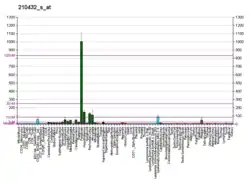

Sodium channel, voltage-gated, type III, alpha subunit (SCN3A) is a protein that in humans is encoded by the SCN3A gene.[5][6]

Voltage-gated sodium channels are transmembrane glycoprotein complexes composed of a large alpha subunit with 24 transmembrane domains and one or more regulatory beta subunits. They are responsible for the generation and propagation of action potentials in neurons and muscle. This gene encodes one member of the sodium channel alpha subunit gene family, and is found in a cluster of five alpha subunit genes on chromosome 2. Multiple transcript variants encoding different isoforms have been found for this gene.[6]

SCN3A is involved in gyrification – the folding of the human cerebral cortex, and affects speech production brain areas.[7]